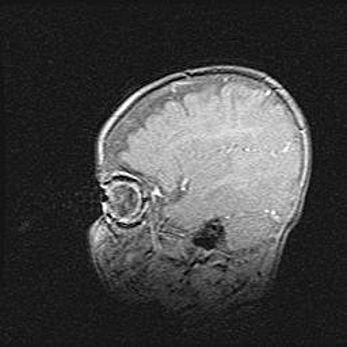

Мальформация Денди-Уокера. Киста задней черепной ямки.

Агенезия мозолистого тела.

Возраст: 2,5 месяца

Вес: 2420 г

Пол: женский

Окружность головы: 37 см

Срок гестации: 32 недели

Мальформация Денди—Уокера — редкий вид патологии ЦНС, представляющий собой врожденный порок развития каудального отдела ствола и червя мозжечка, ведущий к неполному раскрытию срединной (Мажанди) и латеральных (Лушка) апертур IV желудочка мозга. Для этогно синдрома характерна триада симптомов: гипотрофия червя мозжечка и/или полушарий мозжечка, кисты задней черепной ямки, гидроцефалия различной степени. В 70% случаев порок сочетается и с другими аномалиями головного мозга, в частности с агенезией мозолистого тела.